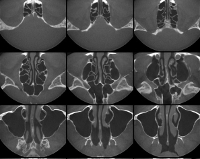

КТ околоносовых пазух

Продолжительность компьютерной томографии околоносовых пазух составляет около 10 минут. Серия изображений расшифровывается рентгенологом, интерпретация занимает около 30-60 минут. Результат исследования представляется пациенту в распечатанном виде, кроме того, его можно записать на любой цифровой носитель (CD-ROM, USB). Важно понимать, что рентгенолог не проводит диагностику, а лишь составляет мнение экспертов о результатах КТ. Диагноз ставится отоларингологом или другим специалистом, который назначил направление для исследования.

Процедура показана при подозрительных опухолях, полипах и кистах околоносовых пазух, что дает четкое представление о структуре и пределах новообразования. В некоторых случаях манипуляции выполняются с жалобами на головные боли, причина которых не обнаруживается другими средствами (например, на ЭЭГ). Показаниями к назначению сканирования придаточных пазух носа могут быть постоянные носовые кровотечения, не находящие объяснения по результатам риноскопии и других исследований. Оцифровка может быть выполнена при воспалительных заболеваниях околоносовых пазух. Методика применяется при недостаточной компьютеризации стандартной рентгенографии, а также при планировании операции на пазухах.